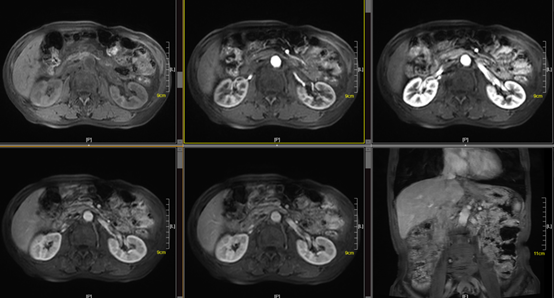

MRI增强

而MRI增强常用的是钆对比剂,钆对比剂(如钆喷酸葡胺)具有顺磁性,能在体内改变周围组织的磁场环境,缩短局部组织中质子的T1和T2弛豫时间,从而在T1WI上产生更高信号,从而改变MRI图像的对比度。MRI在诊断肿瘤性病变、判断肿瘤分期、评估治疗效果有着越来越重要的地位。但MRI检查费用稍高,检查时间较长。此外,MRI检查依靠磁场与射频脉冲,没有辐射的危害。